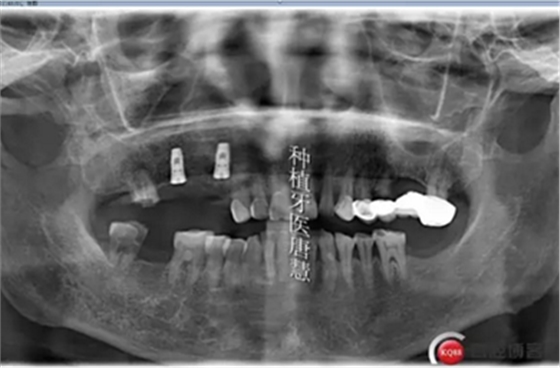

患者劉xx,女,55歲,右上后牙區(qū)殘根,來診咨詢種植。

查見14、15、17殘根狀,松動II°,叩診不適,根尖區(qū)有大面積陰影;16、47缺失,48大面積齲壞

治療計劃:拔除14、15、17、48,種植14、16、17、固定修復(fù),47種植修復(fù),患者要求先種植14、16兩顆